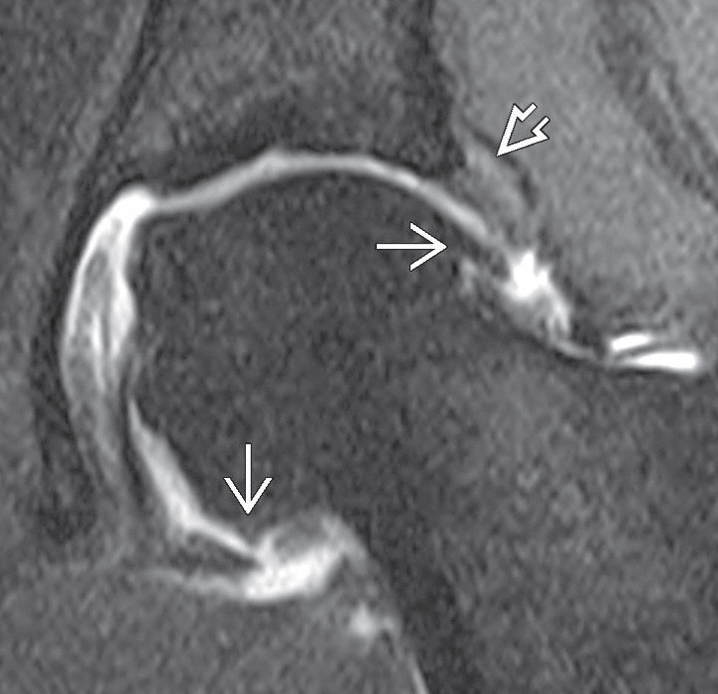

Kalça artrozunda kıkırdak lezyonunu gösteren MR görüntüsü